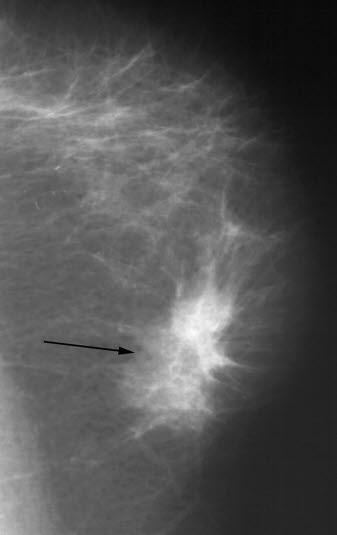

Mammografi, cancer

Skrått mammografibilde som viser en fortetning (pil) med stripeformede drag ut i vevet rundt. Typisk utseende ved brystkreft